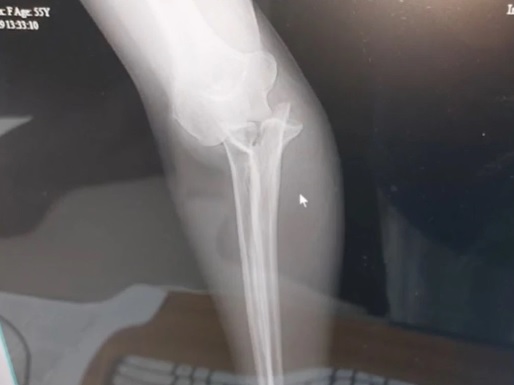

turis asal Amerika Serikat bernama Beth Bogar dari New Hampshire yang mengalami patah tulang akibat berpose dengan gajah di Bali. SP/ BLI

Tapi ketika lengannya mulai membengkak, dia dilarikan ke rumah sakit lebih dari satu jam untuk menjalani operasi darurat. Dokter memasangkan plat dan sekrup untuk menyatukan kembali lengannya.